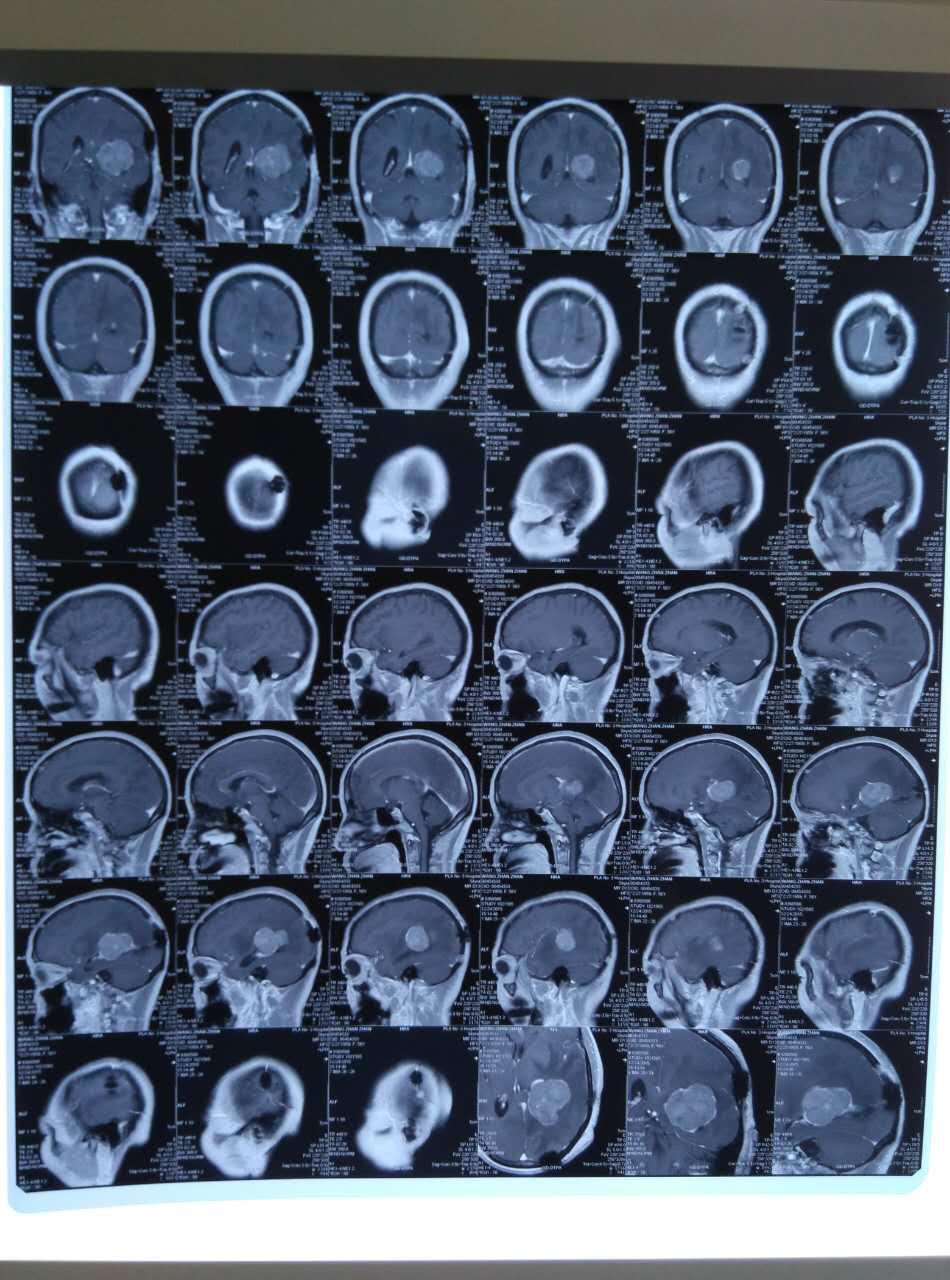

患者,女性,今年56岁,主因头痛、呕吐、视力下降严重就诊,后行脑瘤切除手术。既往有乳腺癌病史,已手术切除。

患者半年前因头痛、呕吐、视力下降严重就诊于附近某医院,行头颅MR平扫+CT示颞叶占位性病变,考虑为胶质瘤,入院后在全麻下进行颞叶占位性病变切除手术,术后病理胶质瘤2级。一周前,患者精神差,伴左侧上眼睑下垂,视力下降严重。为治疗,就诊于第四军医大学唐都医院神经外科,经影像学检查后诊断:胶质瘤复发,肿瘤较大,贾主任结合患者病史建议患者住院进行全面仔细检查,进行二次手术治疗。